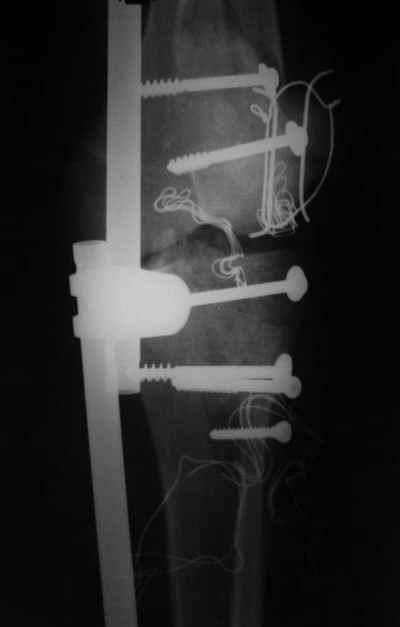

ET> обработку и внешнюю фиксацию, картинки в приложении.

Вид раны на сегодня...

4 cутки после травмы.